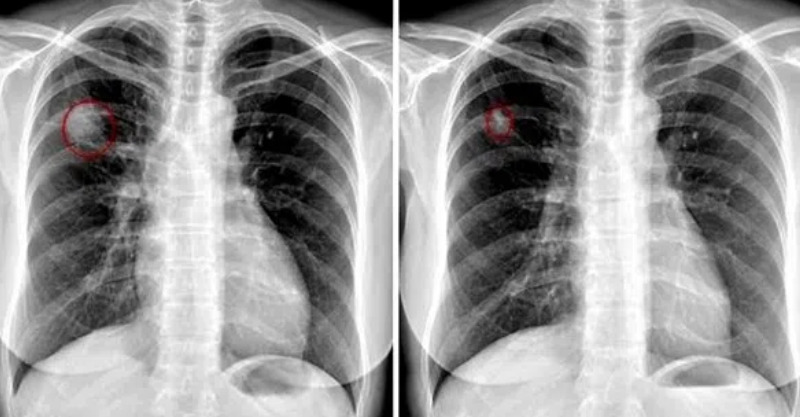

示意圖好險網